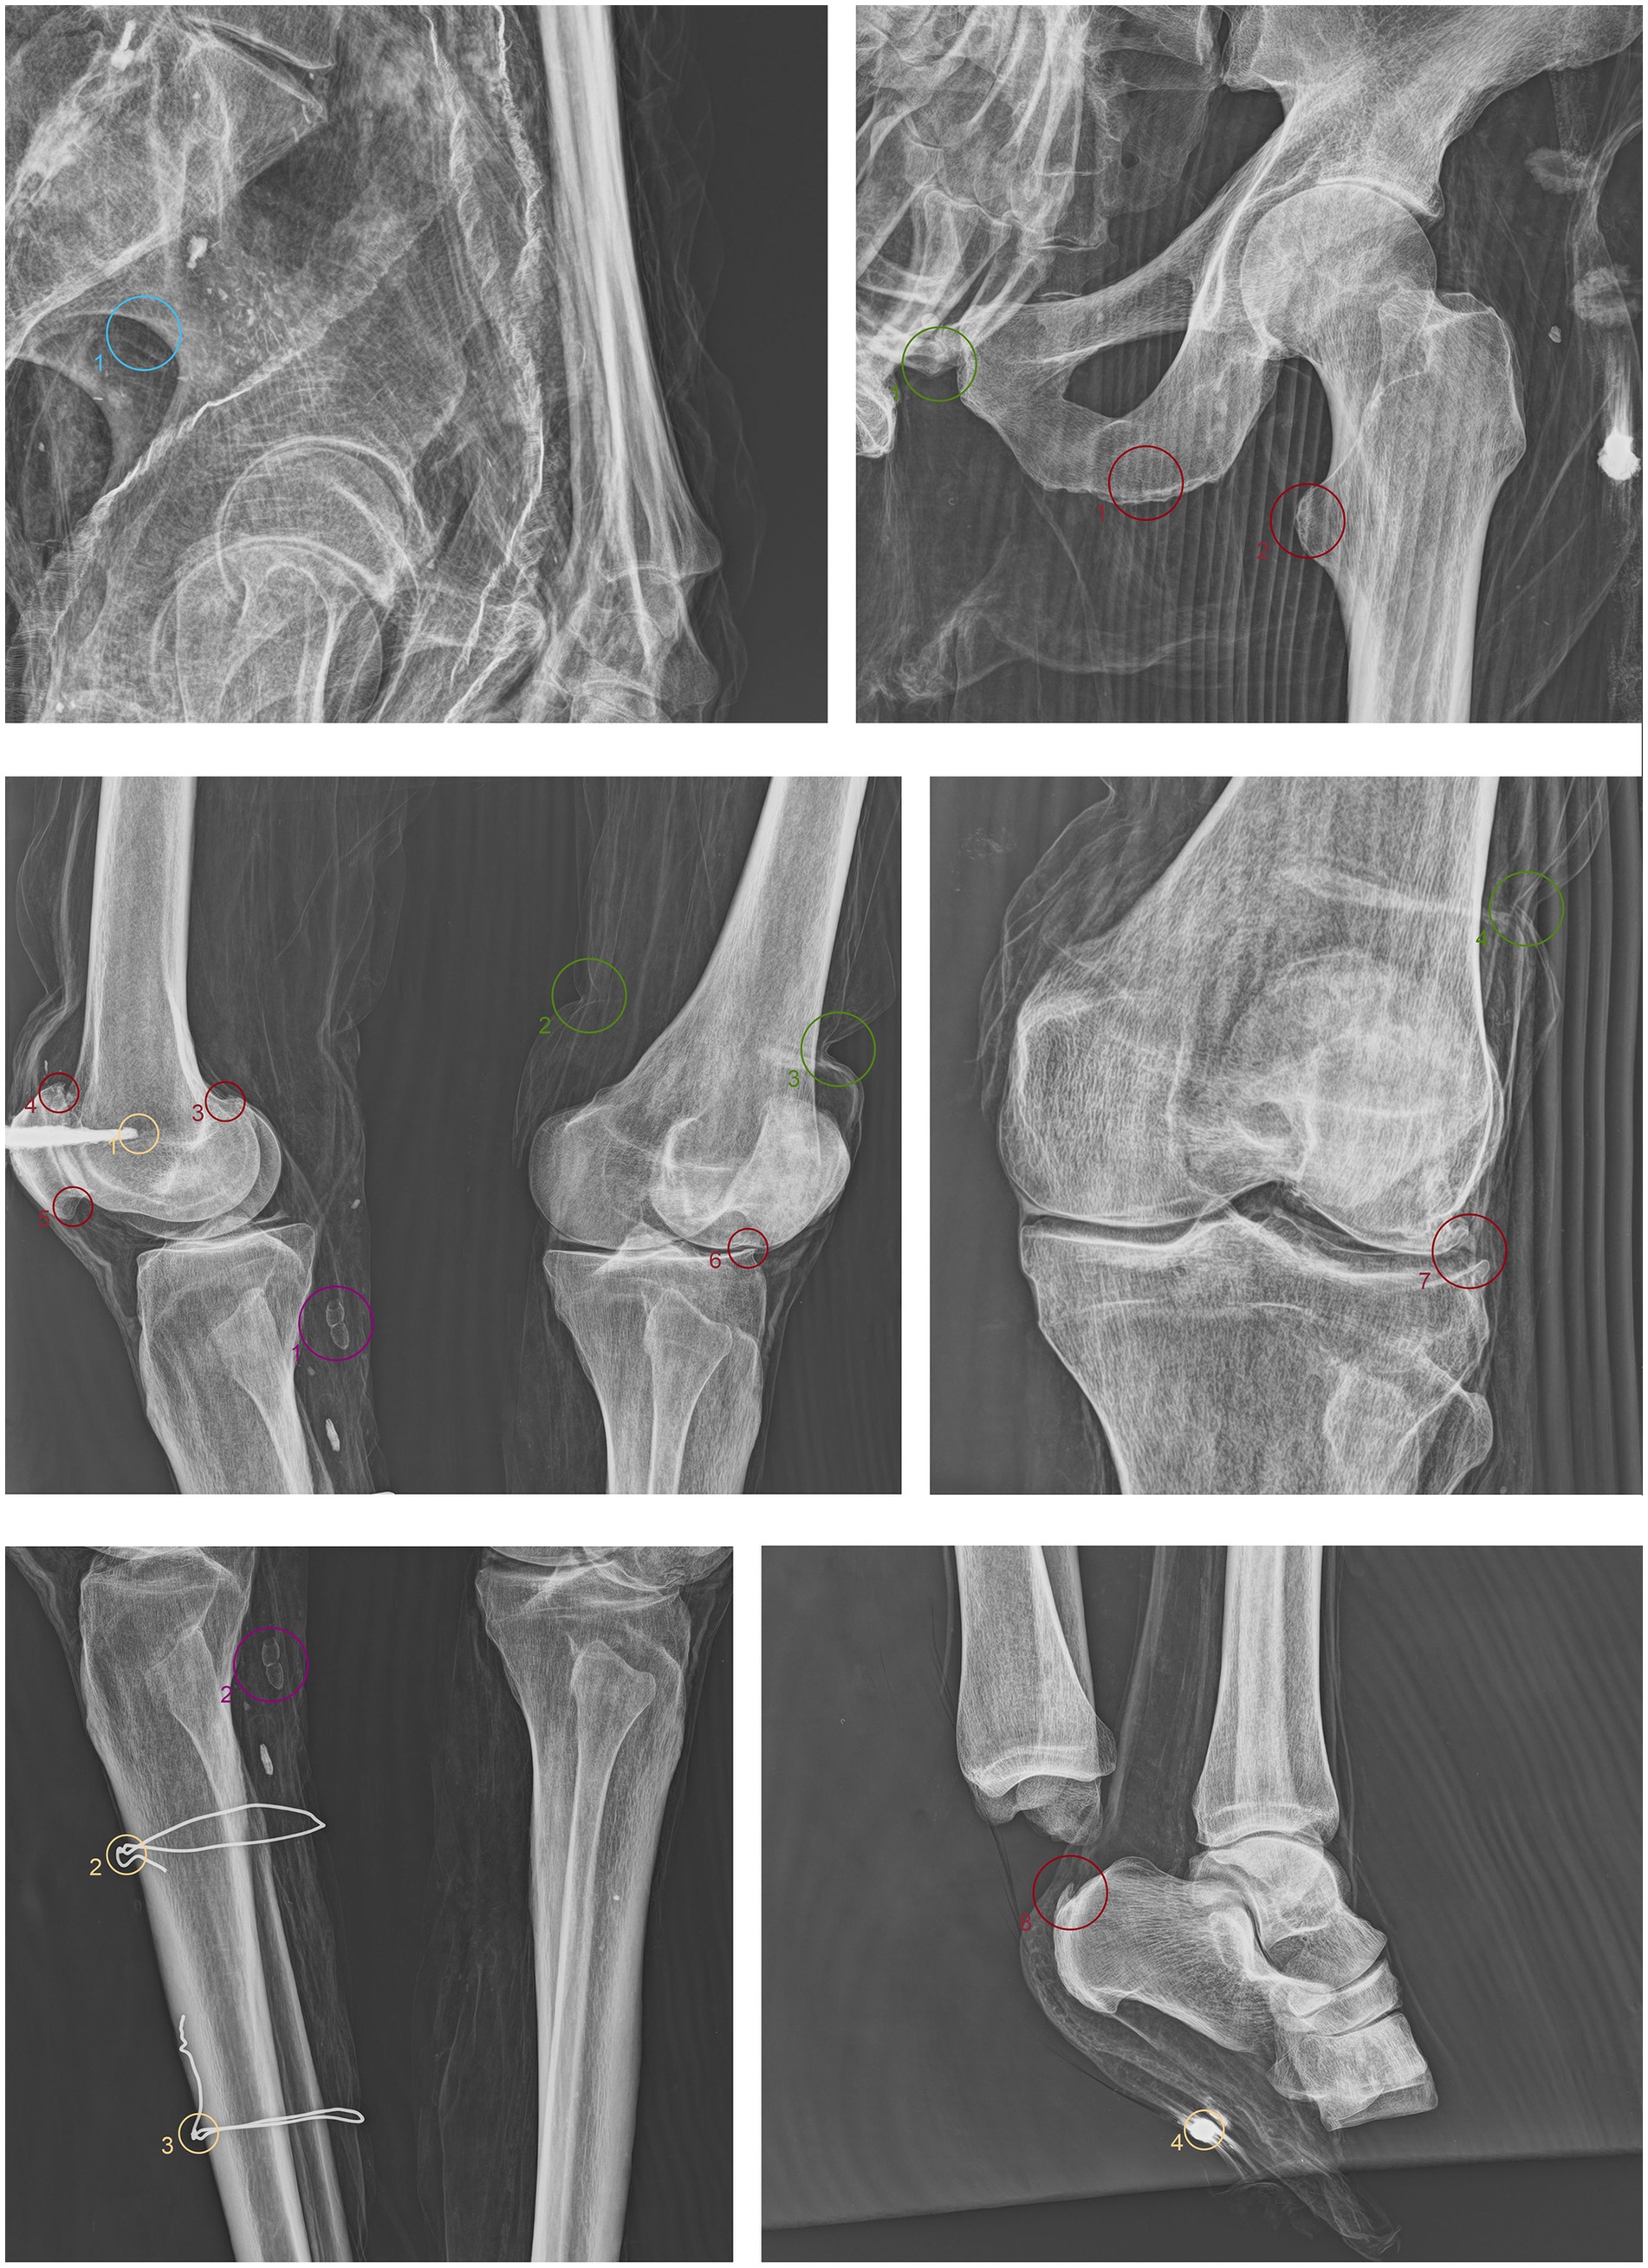

ID1. In the neurocranium, fine material occupies the base, partially filling the occipital region in a layer parallel to the deposition plane (Figure 4.1,5 green). The left frontozygomatic suture is notably more pronounced than the contralateral side due to a slight clockwise rotation of the frontal bone away from the zygomatic bone (Figure 4.2 green). The mandible is also displaced from its anatomical position, with a counterclockwise rotation, pivoting on the mandibular condyle and resulting in the dislocation of the contralateral side (Figure 4.3,6 green). All teeth are absent except for the left upper second premolar (Figure 4.7 green). Other teeth are visible on the floor of the nasopharynx and within the thoracic cavity, to the left of the tenth and eleventh thoracic vertebrae (Figure 4.4,8–10 green). The proximal phalanx of the right thumb is not in anatomical position (Figure 4.11 green), and both distal epiphyses of the fibulae are lacking (Figure 4.12,13 green).

Figure 4. Anteroposterior and lateral radiographic acquisitions of the individual ID1. Green highlights indicate areas of interest for taphonomic study, yellow highlights indicate areas relevant to the assessment of restorations predating this study, violet is used for entomological analysis, blue for anthropological aspects, and red for paleopathological evidence.

ID1. The metal nails within the wooden support boards for the mummy are visible (Figure 4.1,9,13,14 yellow). Metal wire appears on various sections of the body; on the mandible, the wire appears unfastened, and numerous fragments of similar wire are visible at the shoulder level (Figure 4.2–8 yellow). Several loops of metal wire connect the left humerus, ulna, and radius, loosely knotted at the elbow (Figure 4.10–12 yellow).

3.4 Entomological analyses

The search for entomological evidence from the X-rays carried out on the three bodies revealed only a few interesting elements, in contrast to the data obtained from the hand collection of insects and their fragments from the bodies (data not published). In particular, a pair of barrel-like elements of a size (<1 cm) compatible with puparia are visible on ID1 at the pelvis cavity (Figure 4.1,2 violet). The elements are radio-dense and can be interpreted as whole puparia, with the dead immature insects inside or with rat/mouse excrements. In addition, two amphora-like elements are detectable on the leg of ID2 (Figure 6.1,2 violet). These elements are comparable with black mud-dauber wasps’ nests, however, due to their position no direct observations were carried out. So, this remains a potential hypothesis.

ID1. In the lateral view, the pronounced glabella, well-defined nuchal crest, and the right angle formed by the mandibular ramus and body are evident (Figure 4.1–3 blue). The lambda suture appears completely open (Figure 4.4 blue). The sternocostal surfaces of the ribs are well-defined and free from deformities, erosions, or marginal sclerosis (Figure 4.5 blue). The sciatic notch is narrow, and the subpubic angle is less than 90° (Figure 4.6 blue). The cortical thickness of both femoral diaphyses suggests robust bone trophism (Figure 4.7 blue).

3.6 Paleopathological analyses

ID1. X-ray lateral projection analysis of the skull reveals areas of reduced radiodensity that follow the course of the middle meningeal artery, suggesting the presence of a deep groove corresponding to the vessel’s anatomy (Figure 4.1 red). ID1. The X-ray lateral projection of the skull shows areas of reduced radiodensity along the path of the middle meningeal artery, indicating a pronounced groove that aligns with the artery’s course (Figure 4.1 red). In the lower thoracic spine, there are calcifications of the intervertebral space between the 8th and 11th vertebrae, more expressed toward the lumbar region and particularly evident in the lateral projection (Figure 4.2,3,5,6 red). This condition is not associated with marginal lipping on the edges of the vertebral bodies, nor are there any signs of osteolytic activity on the superior or inferior surfaces of the vertebrae (Figure 4.4 red). Calcifications are also visible starting from the articular sternal surface of ribs (Figure 4.7 red). Heterotopic ossification is observed in the pelvic area, corresponding to the sacroiliac joint surface. The anteroposterior projection of this anatomical region reveals osteophytes along the inferior margins of the joint in the ventral view (Figure 4.8,9 red). The non-closure of the sacral laminae up to S3 is also documented (Figure 4.19 red). The densification of bone tissue is observed in the distal diaphysis of both tibiae, approximately 1.7 cm from the distal articular surface (Figure 4.11,12 red).